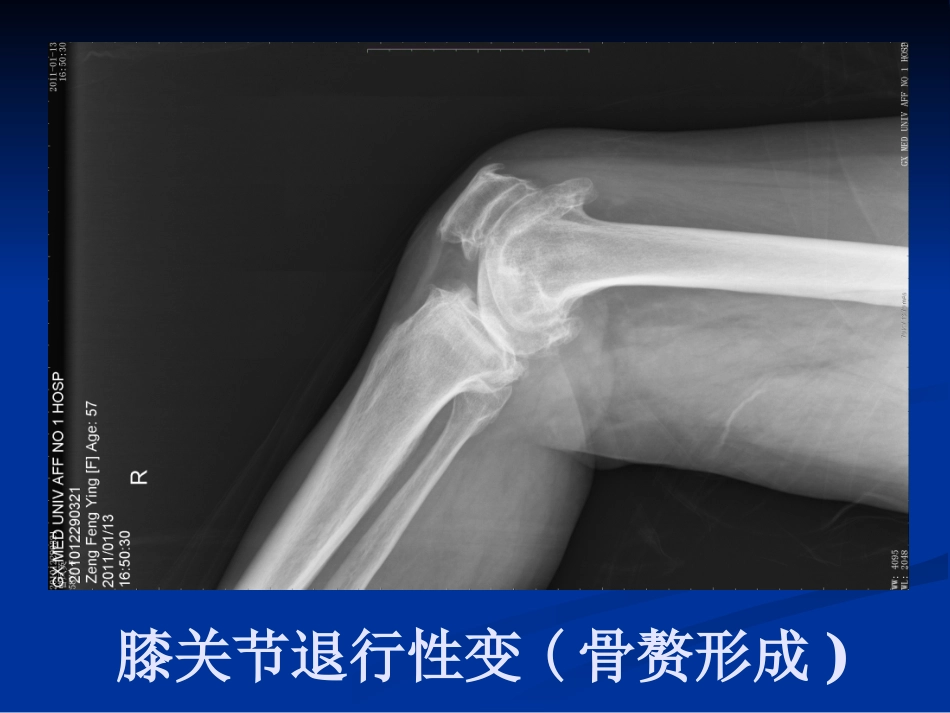

膝关节骨性关节炎昌吉州中医院针灸科昌吉州中医院针灸科孙存海孙存海膝关节退行性变(胫骨平台软骨下钙化)膝关节退行性变(骨赘形成)膝关节退行性变(半月板钙化、膝关节变形)在膝骨性关节炎的初期,由于大部分症状多为隐匿性,即使疼痛也是比较轻微或时好时坏,因此大部分病人并不在意。而恰在此时,由于一些不当的生活方式或工作习惯常常导致本病的进一步发展。到了膝关节骨性关节炎病变的中晚期,疼痛和关节活动受限常常严重影响骨性关节炎患者的日常生活和工作,有时甚至连走路这样简单的活动也会觉得非常困难。由于骨性关节炎的病程是逐渐进展的,关节疼痛和僵硬会随着时间的延长而加重,加之大部分患者对相关的医学知识了解有限,不能采取及时得当的治疗及预防措施,更容易使患者的病情进一步加重,从而...